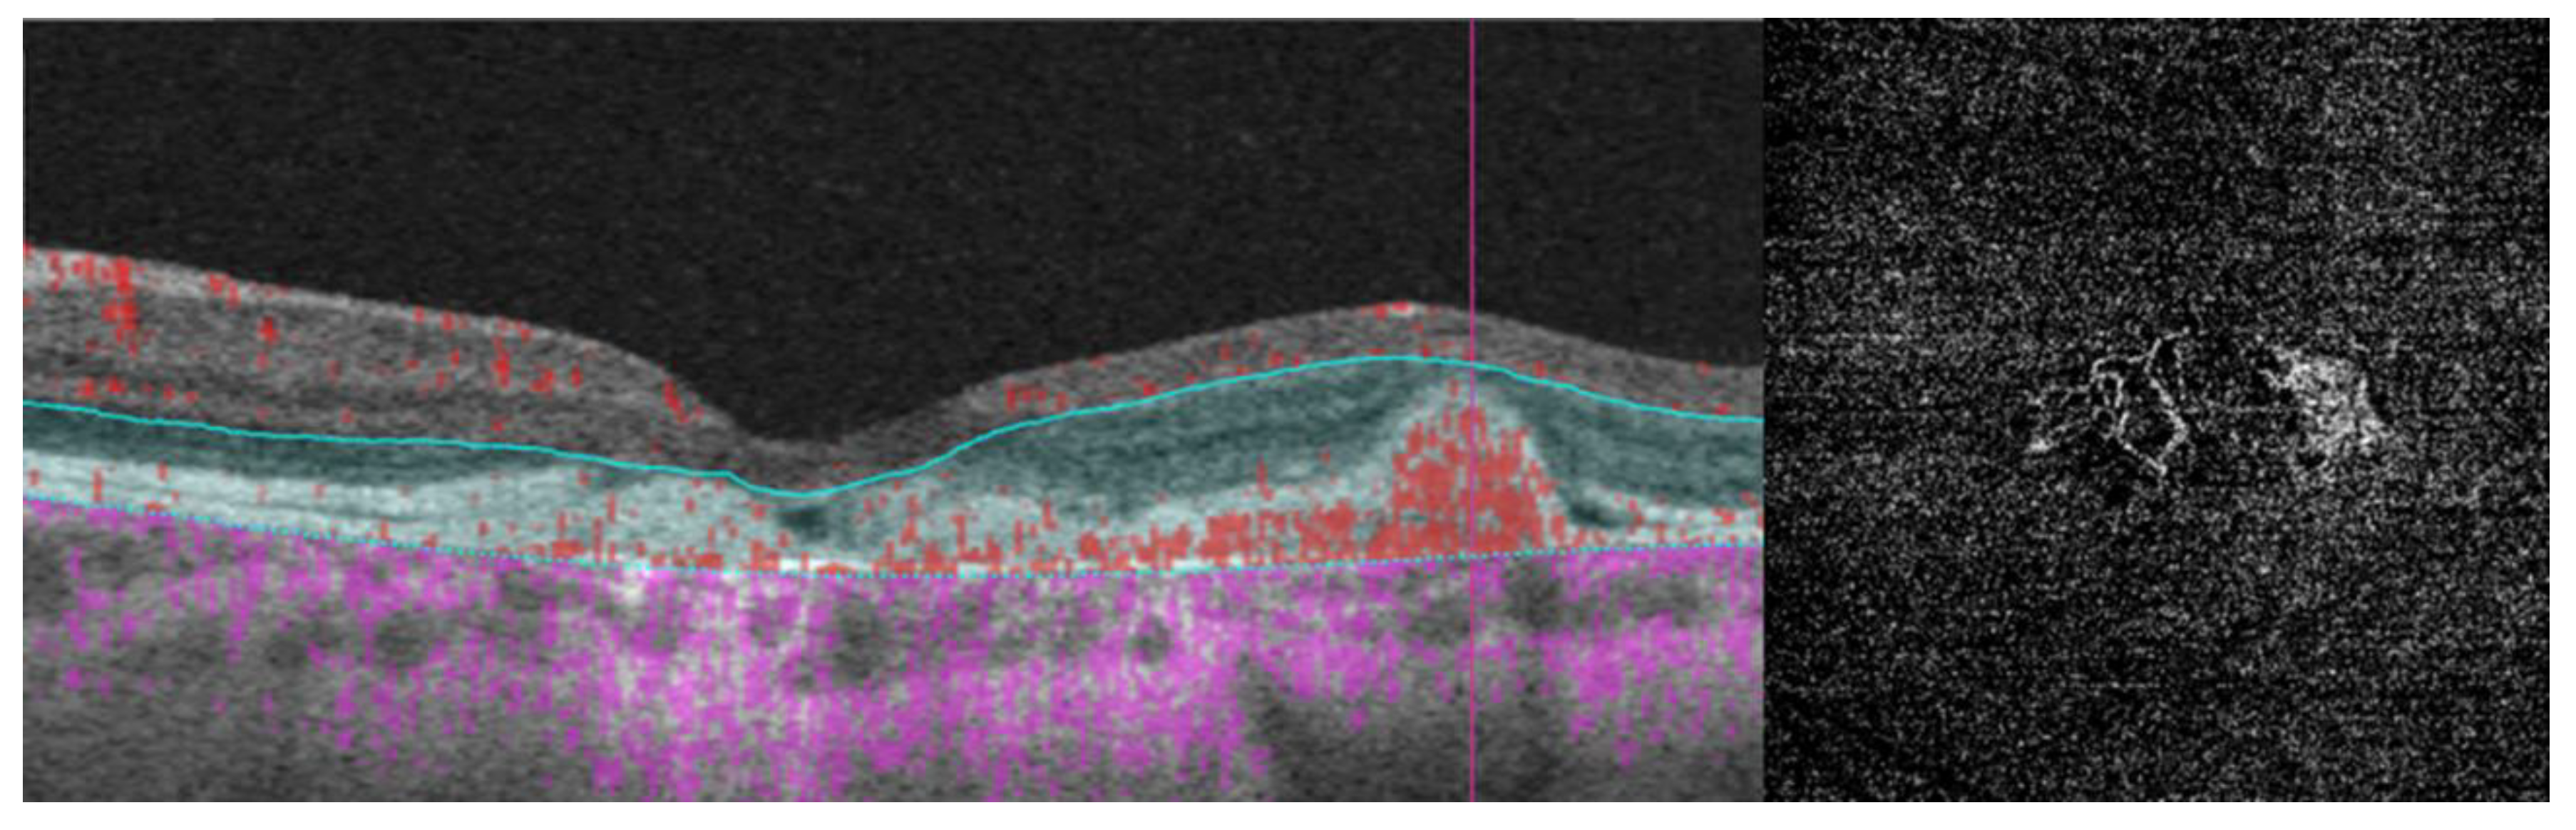

3. Best Vitelliform Macular Dystrophy

- Retinal hyperreflective foci (HRF) are punctiform lesions, typically smaller than 30 μm, primarily located in the outer nuclear and plexiform layers of the neuroretina. Battaglia Parodi et al. identified the presence of HRF in BVMD and noted an increase in their number as the disease progressed [32]. HRF may constitute accumulations of microglia or RPE cells detached from Bruch’s membrane (BM) and migrated into the subretinal space, eventually reaching the neuroretina [33]. Recent data obtained using polarization-sensitive OCT, which provides tissue-specific contrast, has lent support to the theory by demonstrating the presence of RPE cells within the vitelliform material and the neuroretina. Consequently, HRF appears to reflect the progression of the disease and may serve as a valuable biomarker for monitoring BVMD.

| Best vitelliform macular dystrophy |

|